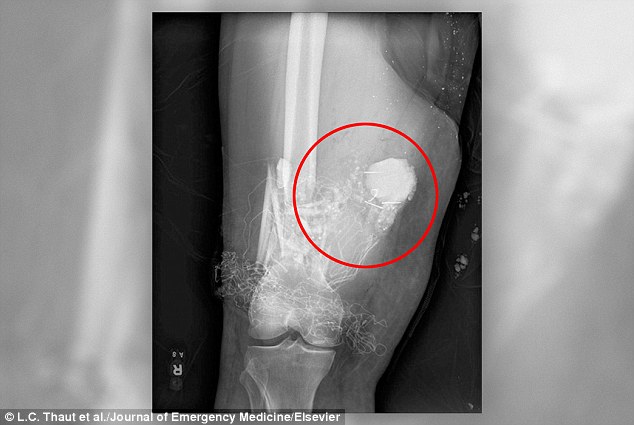

Quả pháo chưa nổ găm trong đùi bệnh nhân ở bang Texas, Mỹ.

Một bệnh nhân 44 tuổi đã được đưa tới bệnh viện quân y San Antonio ở bang Texas, Mỹ, sau khi bị pháo giống như đạn cối găm vào đùi. Kết quả chụp X-quang cho thấy quả pháo có thể nổ bất cử lúc nào.